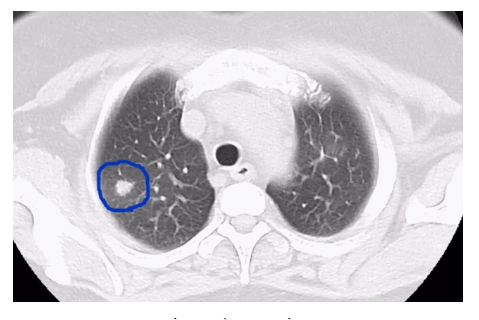

d4f7-izeysaz7113042.gif

Sau khi được chụp CT và kiểm tra về kháng thể ký sinh trùng, bác sĩ nhận ra cả 3 người đều đã nhiễm sán lá phổi. Sán lá phổi là một loại sán ký sinh, thường tấn công vùng phổi nhưng cũng có thể xâm nhập và làm tổn thương màng não, gây đau đầu dữ dội, làm teo dây thần kinh mắt, liệt nhẹ tay chân hoặc rối loạn tâm thần. Nếu không cấp cứu kịp thời có thể gây nguy hiểm cho tính mạng.